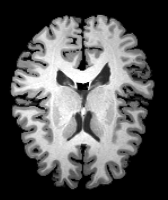

Knee MRI experiment: We test our method on 3D knee MRIs from the Osteoarthritis Initiative (OAI) 111https://nda.nih.gov/oai/ and corresponding segmentations of femur and tibia as well as femoral and tibial cartilage [1]. From a total of 507 labeled images, we use 200 for training, 53 for validation, and 254 for testing. To test registration performance we use 10,000 random image pairs from the test set. All images are affinely registered to an atlas built from the training images, resampled to isotropic spacing of 1mm, cropped to and intensity normalized to [0,1]. In addition, right knee images are flipped to be consistent with left knees. For training, the loss weights are , , and based on approximate hyper-parameter tuning. Note that when computing from the displacements, the image coordinates are scaled to [-1, 1] for each dimension following the convention in the interpolation function of PyTorch.

Results: All trained networks are evaluated using Dice overlap scores between predictions and the manual segmentations for the segmentation network, or between the warped moving segmentations and the target segmentations for the registration network. Tabs. 1 and 2 show results for the knee and brain MRI experiments respectively in Dice scores (%). Fig. 2 shows examples of knee MRI registrations and brain MRI segmentations.

Knee results: On knee MRIs, our method improves segmentation scores over separately learned networks by about 1.2 and 0.5, and registration scores increase by about 3.1 and 3.0, when training with 5 and 10 manual segmentation respectively. Especially for the challenging cartilage structures, our joint learning boosts segmentation by 1.4 and 0.7, and registration by 5.5 and 5.2 for N=5 and N=10 respectively.

Qualitative results: DA achieves more anatomically consistent registrations than the mono-networks on the knee (Fig. 2) and Brain MRI samples (see supplementary material).